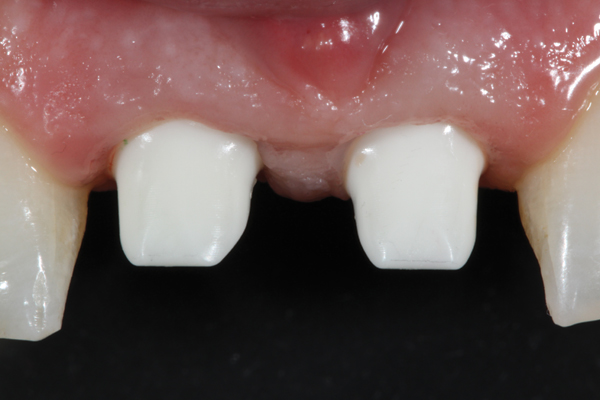

Fig 2. The esthetic zone often presents with the challenge of two adjacent edentulous spaces. Use of two implants creates a stronger restorative solution, but at the expense of the inter-implant papilla. The average papilla height between adjacent implants is a mere 3.4 mm.

Figure 2